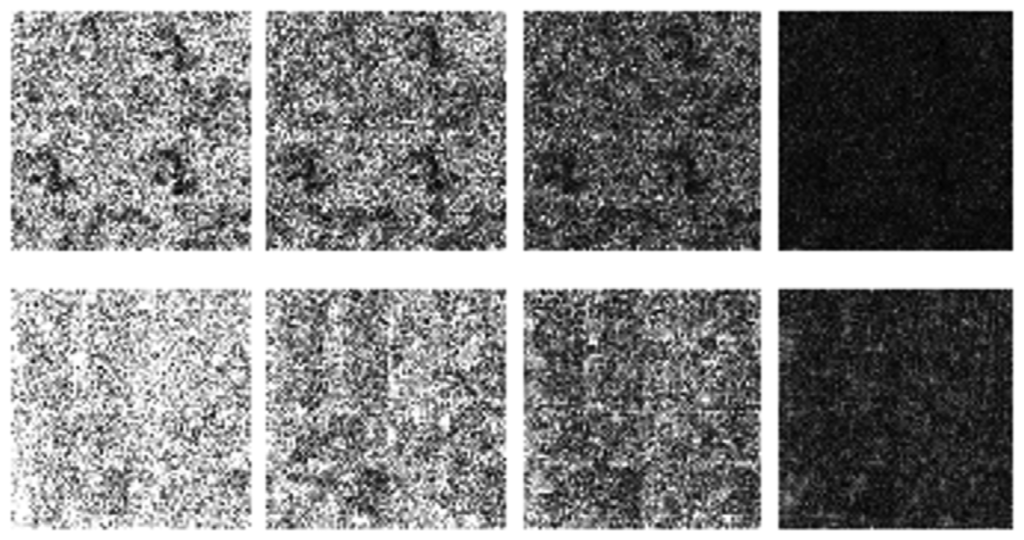

The differences in the reconstruction quality are best evaluated from the difference images. The difference is formed by taking the absolute difference between the reconstructed and the groundtruth images. The contrast of the difference images is enhanced five times for visual clarity.

The difference in the reconstruction quality is easily discernible in the difference images; see Figures 5 and 6. The difference images that are brighter indicate the presence of higher reconstruction error. We can see that group-sparse recovery using the same Fourier mapping on all the echoes yields the worst reconstruction while our proposed rank-deficient group-sparse recovery (different Fourier map for each echo) yields the best results.